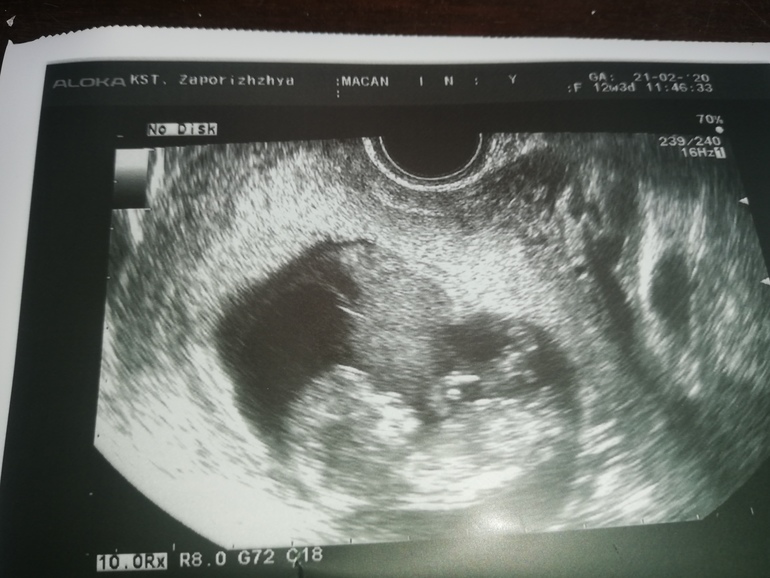

В 12 недель результат неинформативный могут ошибиться. Лучше после 18 -20 недель.

На какой неделе первое узи делали?